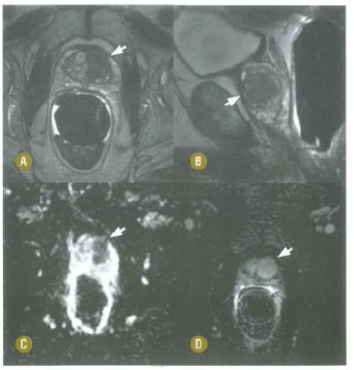

Paciente de 71 anos com aumento do PSA realiza RM com o seguinte resultado. Sobre essa RM, é correto afirmar que